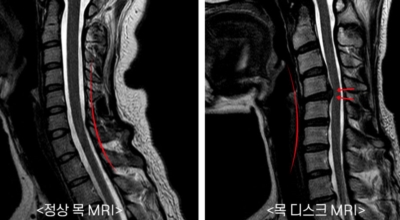

목디스크 증상이 나타날때 빨리 발견하여 비수술 치료를 받고 꾸준히 관리하는 것이 베스트이죠. 목디스크 환자 중 수술을 진행하는 환자는 2% 미만으로 현저히 적다고 해요. 수술을 진행하는 경우는 감각이 느껴지지 않는 마미증후군이나, 한쪽 다리가 눈에 띌 정도로 야윈 경우에만 진행하므로 올바른 자세 교정만으로도 충분히 호전될 수 있는 질병이죠. 목에 연관된 검사는 MRI나 CT를 이용해요. 그러나 전자의 경우 비용이 굉장히 비싸기 때문에 디스크 증세가 확실하다고 생각될 경우에만 선택적으로 하고 의무적으로 하는 건 아니니까 비용에 대해선 부담을 가지지 마시길 바래요.

목디스크는 20대 이후에 자주 발생해요 그 이유는 목에 있는 디스크의 약화와 잘못된 자세에서 비롯되는 경우가 많습니다 위에서 언급드렸듯이 장기간 앉아서 근무한다면 좋지 않은 자세로 인해 목에 무리가 갈 수 있고 평상시에도 바른 자세를 유지하고 있는 것은 굉장히 고통스럽고 힘든 일이라서 목 통증이 느껴지는 건 당연하다고 볼 수 있어요.